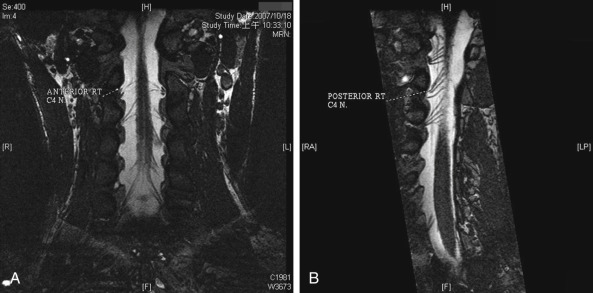

In recent years, invasive imaging studies (such as cervical myelography) are gradually being replaced by non-invasive magnetic resonance imaging (CT-myelogram and 3D-MRI). An MRI study with various investigative techniques is very helpful for diagnosis of root injury. Improved techniques for diagnosis include C-spine MRI myelogram; 3D-FIESTA (Fast Imaging Employing Steady-state Acquisition) study provides rapidly obtained images of fluid-filled structures with continuous slices from the antero-posterior cutting plane ( Fig. 21.2 ), different planes of ventral and dorsal rootlets using curve planar reformat technique; MRI, diffusion weighted imaging (DWI), and short tau inversion recovery (STIR) techniques with views of the Level II–IV nerve structures. Valuable and accurate data provided by the various MRI techniques allow surgeons to make more confident judgments on the level injury of A-BPI.